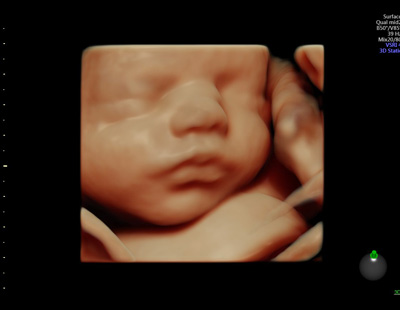

Beratung & Behandlung Mein Angebot geht über die „klassische” Gynäkologie und Behandlung hinaus. Sie umfassend zu beraten ist mir ein ganz wichtiges Anliegen. Denn gerade viele „Frauenprobleme” lassen sich leicht vermeiden, wenn darüber gesprochen wird. |